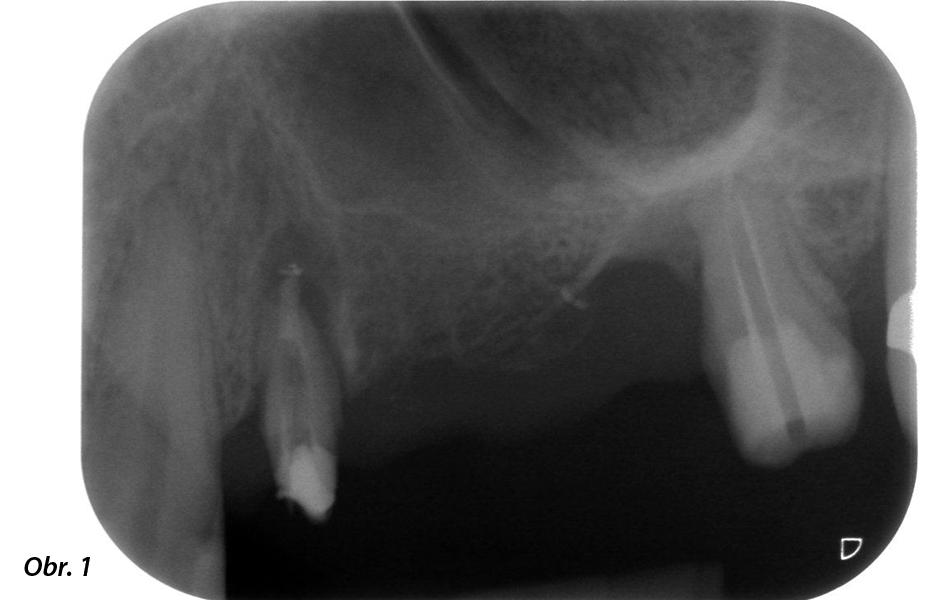

58letá pacientka si stěžovala na bolest a zvýšenou mobilitu pilířového zubu 24. U zubu byl přítomen periodontální zánět s choboty o hloubce 7 mm meziobukálně a více než 12 mm distálně, a také rozvinutá furkace třetího stupně. RTG snímek navíc odhalil rozsáhlou periodontální lézi kolem apikální oblasti (alio loco) dříve endodonticky ošetřeného zubu 24 (obr. 1). Zuby 25 a 26 byly před rokem extrahovány z důvodu úrazu a endodonticko-parodontologických problémů a poté byl v oblasti umístěn můstek. U zubu 24 byla diagnostikována kombinovaná endodonticko-parodontologická léze nejasné etiologie. Pacientka si přála zachovat pilířové zuby 24 a 27, a nechtěla se smířit s definitivní ani provizorní snímatelnou náhradou. Dohodli jsme se proto na tom, že uděláme vše pro zachování obou zubů, a to i přes jejich špatnou prognózu, která vyplynula z radiologického i klinického vyšetření.

58letá pacientka: předoperační RTG snímek zachycující apikální periodontální lézi u zubu 24 a horizontální úbytek alveolární kosti v druhém kvadrantu.